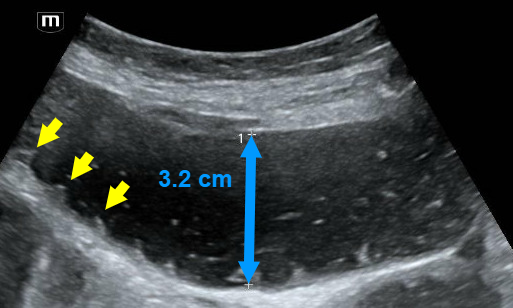

This is small bowel. How do we know this? Note the small finger-like projections from the inner wall (yellow arrows). These are called plicae circulares, which are  mucosal folds of the small intestine. Also note that the bowel diameter is dilated up to 3.2 cm (blue arrow).

·       A small bowel obstruction will also lead to bowel wall edema, which causes a wall thickness > 4 mm. The bowel wall edema and dilated diameter will make the intestinal folds or plicae circulares appear more prominent, leading to the “key board” sign seen in the image above.